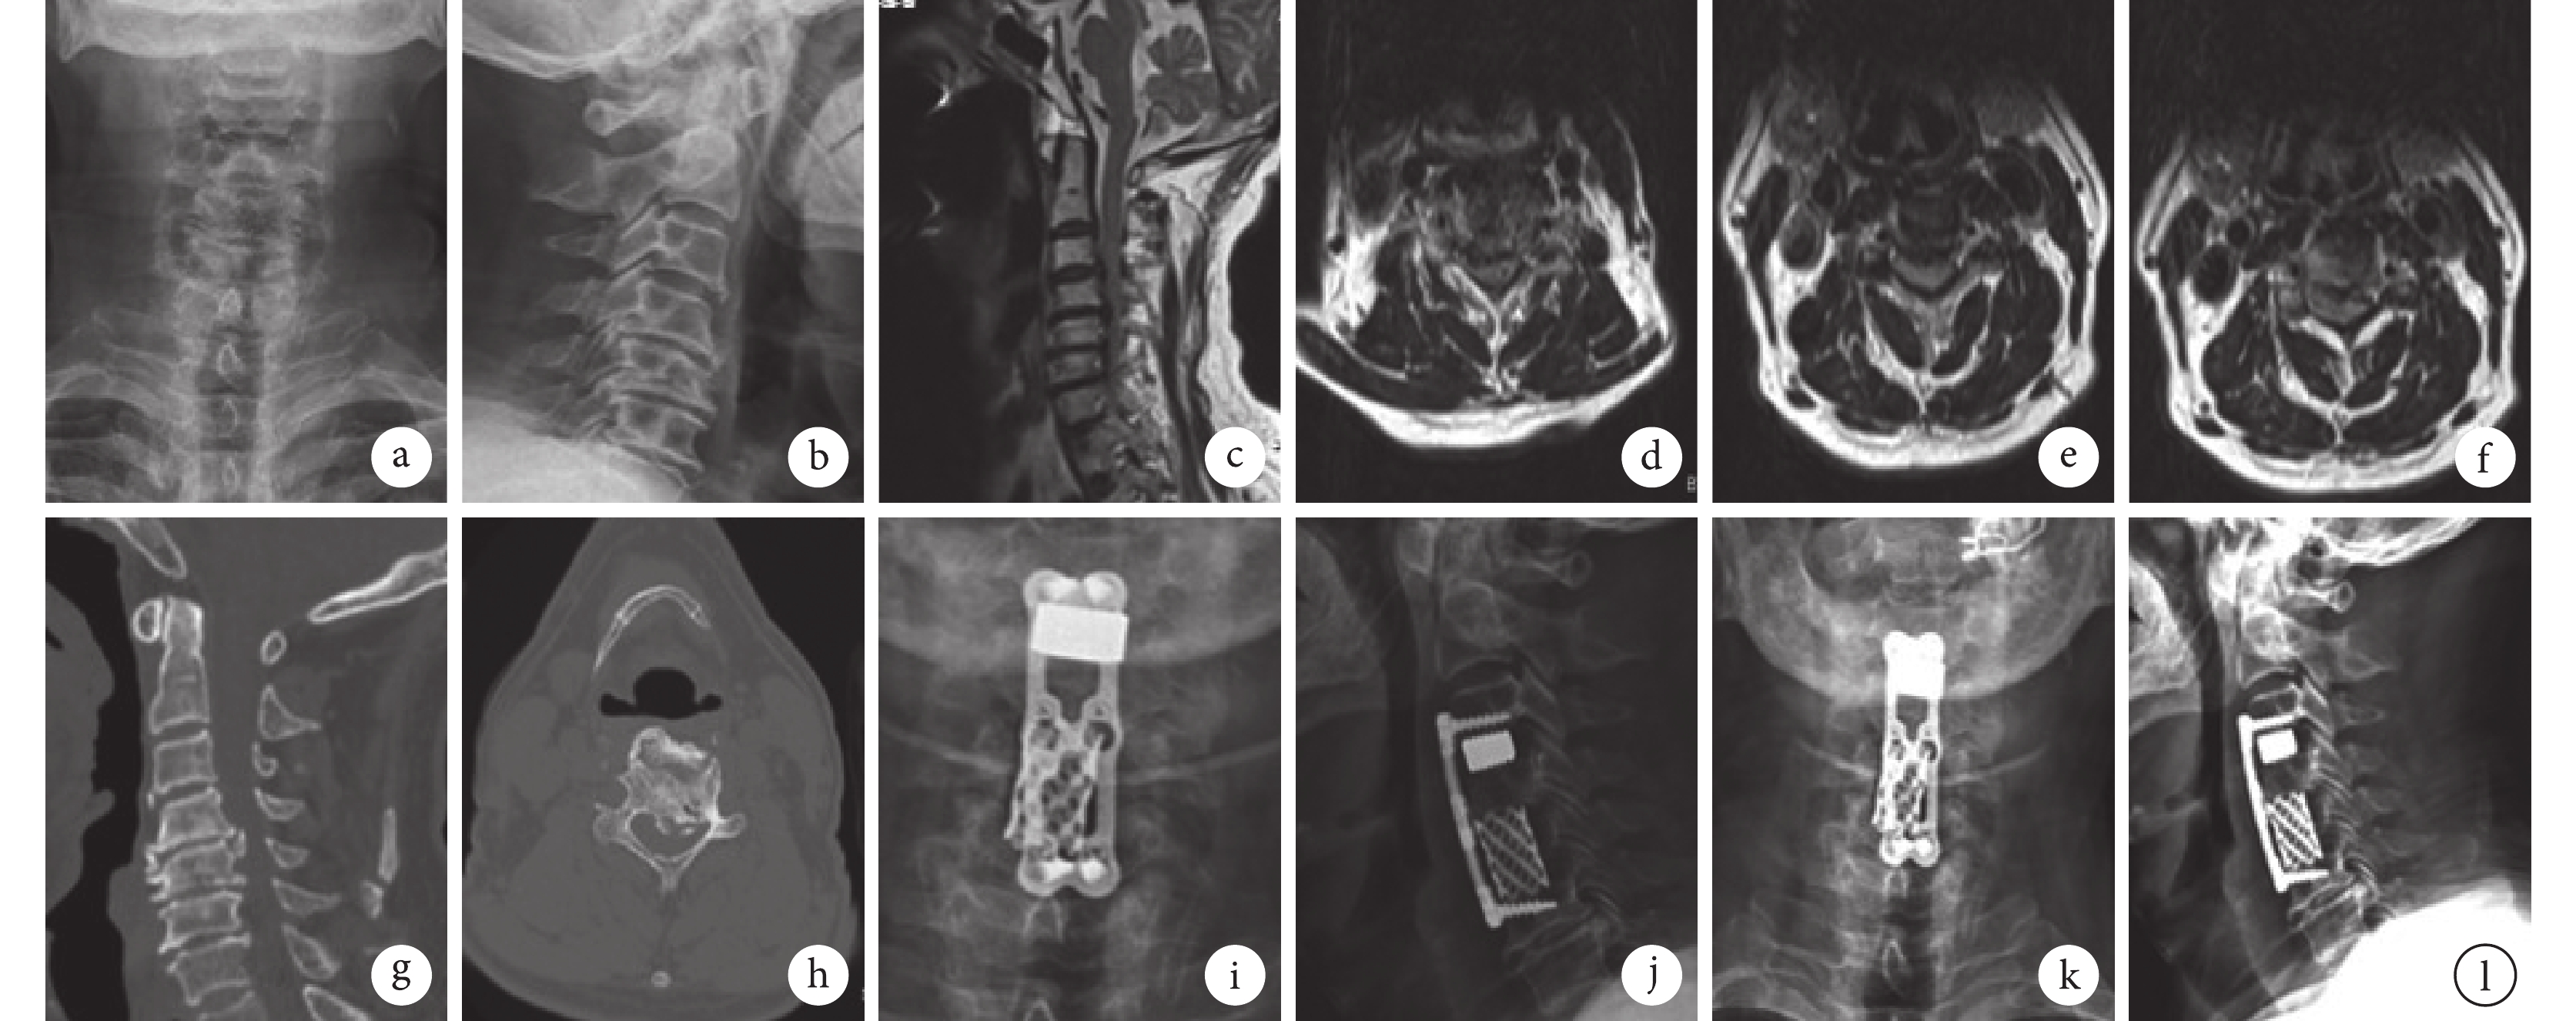

a、b. 術前頸椎正側位X線片;c~f. 術前頸椎矢狀位及C4、5、C5、6、C6、7橫斷位MRI;g、h. 術前頸椎矢狀位及C4、5橫斷位CT;i、j. 術后1個月頸椎正側位X線片;k、l. 術后3個月頸椎正側位X線片

Figure2. A 54-year-old female patient with cervical disc herniation at C4-7 in group Aa, b. Preoperative anteroposterior and lateral X-ray films of the cervical spine; c-f. Preoperative sagittal MRI of the cervical spine and transverse MRI of C4, 5, C5, 6, and C6, 7, respectively; g, h. Preoperative sagittal CT of the cervical spine and transverse CT of C4, 5; i, j. Anteroposterior and lateral X-ray films of the cervical spine at 1 month after operation; k, l. Anteroposterior and lateral X-ray films of the cervical spine at 3 months after operation

兩組患者均獲隨訪,隨訪時間6~12個月,平均7.9個月。組內比較:術后兩組JOA評分及改善率均逐漸升高、VAS評分及NDI逐漸降低,除B組術后3個月VAS評分與1個月差異無統計學意義(P>0.05)外,兩組各指標其余時間點間比較差異均有統計學意義(P<0.05)。組間比較:術后1、3、6個月B組JOA評分及改善率均優于A組,差異有統計學意義(P<0.05)。見圖1。X線片復查示兩組術后均無螺釘松動、鈦板移位,椎間融合器或鈦網明顯下沉發生。見圖2、3。